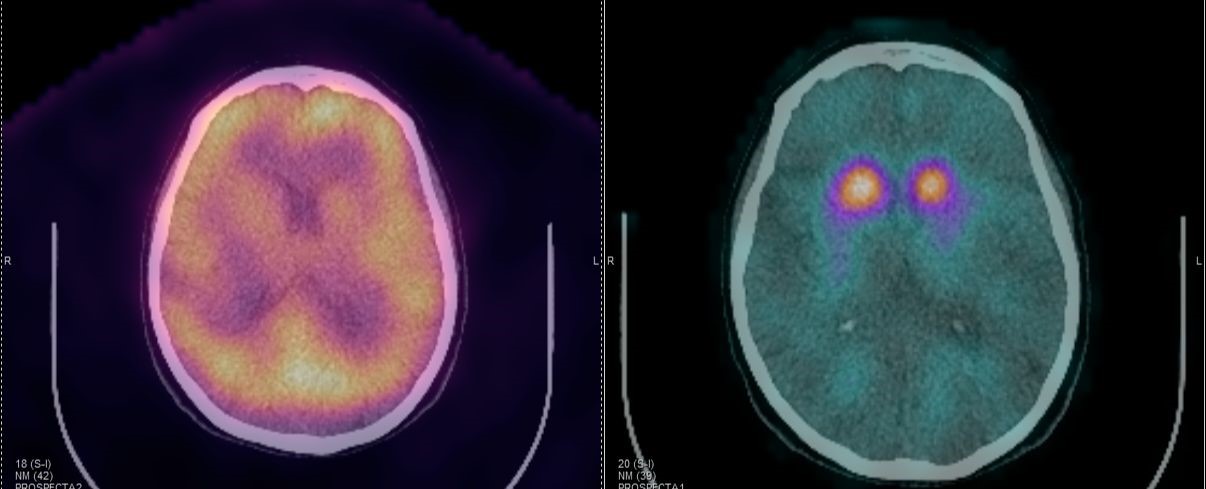

Οι περισσότερες διαγνωστικές εξετάσεις της Πυρηνικής Ιατρικής είναι γνωστές ως σπινθηρογραφήματα, τα οποία στη σύγχρονη εποχή πραγματοποιούνται με τη βοήθεια της γ-κάμερας (γ-camera) ή συστημάτων SPECT/CT, που επιτρέπουν απεικόνιση υψηλής ακρίβειας και λειτουργική ανάλυση σε μοριακό επίπεδο.

Tο Νοσοκομείο ΥΓΕΙΑ είναι το μοναδικό με πάνω από 15 χρόνια εμπειρία στην SPECT CT Aπεικόνιση. Από το 2024 διαθέτει δύο υπερσύγχρονες τομογραφικές γ-κάμερες της Siemens – Symbia Pro.specta SPECT/CT with myExam Companion. Πρόκειται για συστήματα τελευταίας γενιάς που συνδυάζουν υψηλή απεικονιστική ακρίβεια, χαμηλή δόση ακτινοβολίας και πλήρη αυτοματοποίηση της διαδικασίας. Με την χρήση ειδικού σύγχρονου λογισμικού (SIEMENS SYNGO) εξασφαλίζεται η μέγιστη ποιότητα εικόνας. Ειδικότερα οι γ-κάμερες χαρακτηρίζονται από τα εξής:

Όλες οι μελέτες Πυρηνικής Ιατρικής πραγματοποιούνται με SPECT/CT μέθοδο στις 2 υπερσύγχρονες SIEMENS Pro SPecta. Από το δυσδιάστατο στο τρισδιάστατο, από την υπόνοια στη βεβαιότητα.

Το Lu-177 PSMA αποτελεί μια στοχευμένη ραδιονουκλιδική θεραπεία για ασθενείς με ορμονοάντοχο μεταστατικό καρκίνο του προστάτη (mCRPC), αξιοποιώντας τη υπερέκφραση του PSMA (Prostate-Specific Membrane Antigen) στα καρκινικά κύτταρα. Προηγείται PSMA PET/CT για ακριβή χαρτογράφηση της νόσου και επιβεβαίωση επαρκούς πρόσληψης του ραδιοφάρμακου. Το Lu-177 PSMA συνδέεται στους PSMA-υποδοχείς, επιτρέποντας στοχευμένη ακτινική δράση υψηλής κυτταροτοξικότητας σε μεταστατικές εστίες οστών και μαλακών μορίων. Η χρήση εξειδικευμένων δοσιμετρικών εργαλείων επιτρέπει την ποσοτική αποτίμηση της δόσης σε κρίσιμα όργανα (π.χ. σιελογόνοι αδένες, νεφροί, μυελός) και στον όγκο, συμβάλλοντας σε εξατομικευμένη θεραπευτική προσέγγιση. Μετά από κάθε κύκλο πραγματοποιείται PSMA PET/CT ή FDG PET/CT (όπου ενδείκνυται), καθώς και στενός αιματολογικός έλεγχος για αξιολόγηση της ανταπόκρισης και των πιθανών τοξικοτήτων. Η θεραπεία έχει αποδειχθεί ιδιαίτερα αποτελεσματική στη μείωση του καρκινικού φορτίου, στη βελτίωση του πόνου, στη μείωση των επιπέδων PSA και στη σημαντική παράταση του προσδόκιμου επιβίωσης σε ασθενείς με εκτεταμένη και ανθεκτική νόσο.